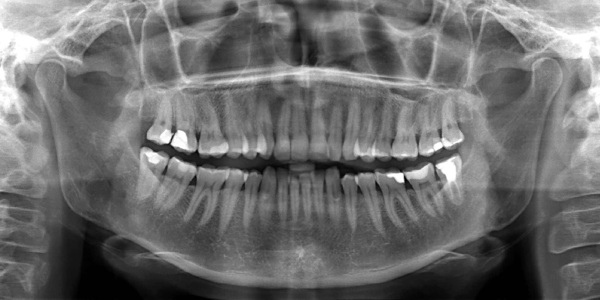

Для полной оценки состояния челюсти и зубного ряда врач может порекомендовать прохождение особой процедуры для получения снимка – ортопантомограммы. На основании полученных данных пациенту будут выданы конкретные рекомендации.

Они могут включать следующие процедуры:

- профессиональная чистка для полного устранения налета и отложений камня;

- обтачивание зубов для капитальной фиксации коронок и протезов;

- восстановление целостности десневых карманов;

- удаление всех очагов кариозных поражений;

- снятие симптомов кровоточивости десен;

- синус-лифтинг перед имплантированием.